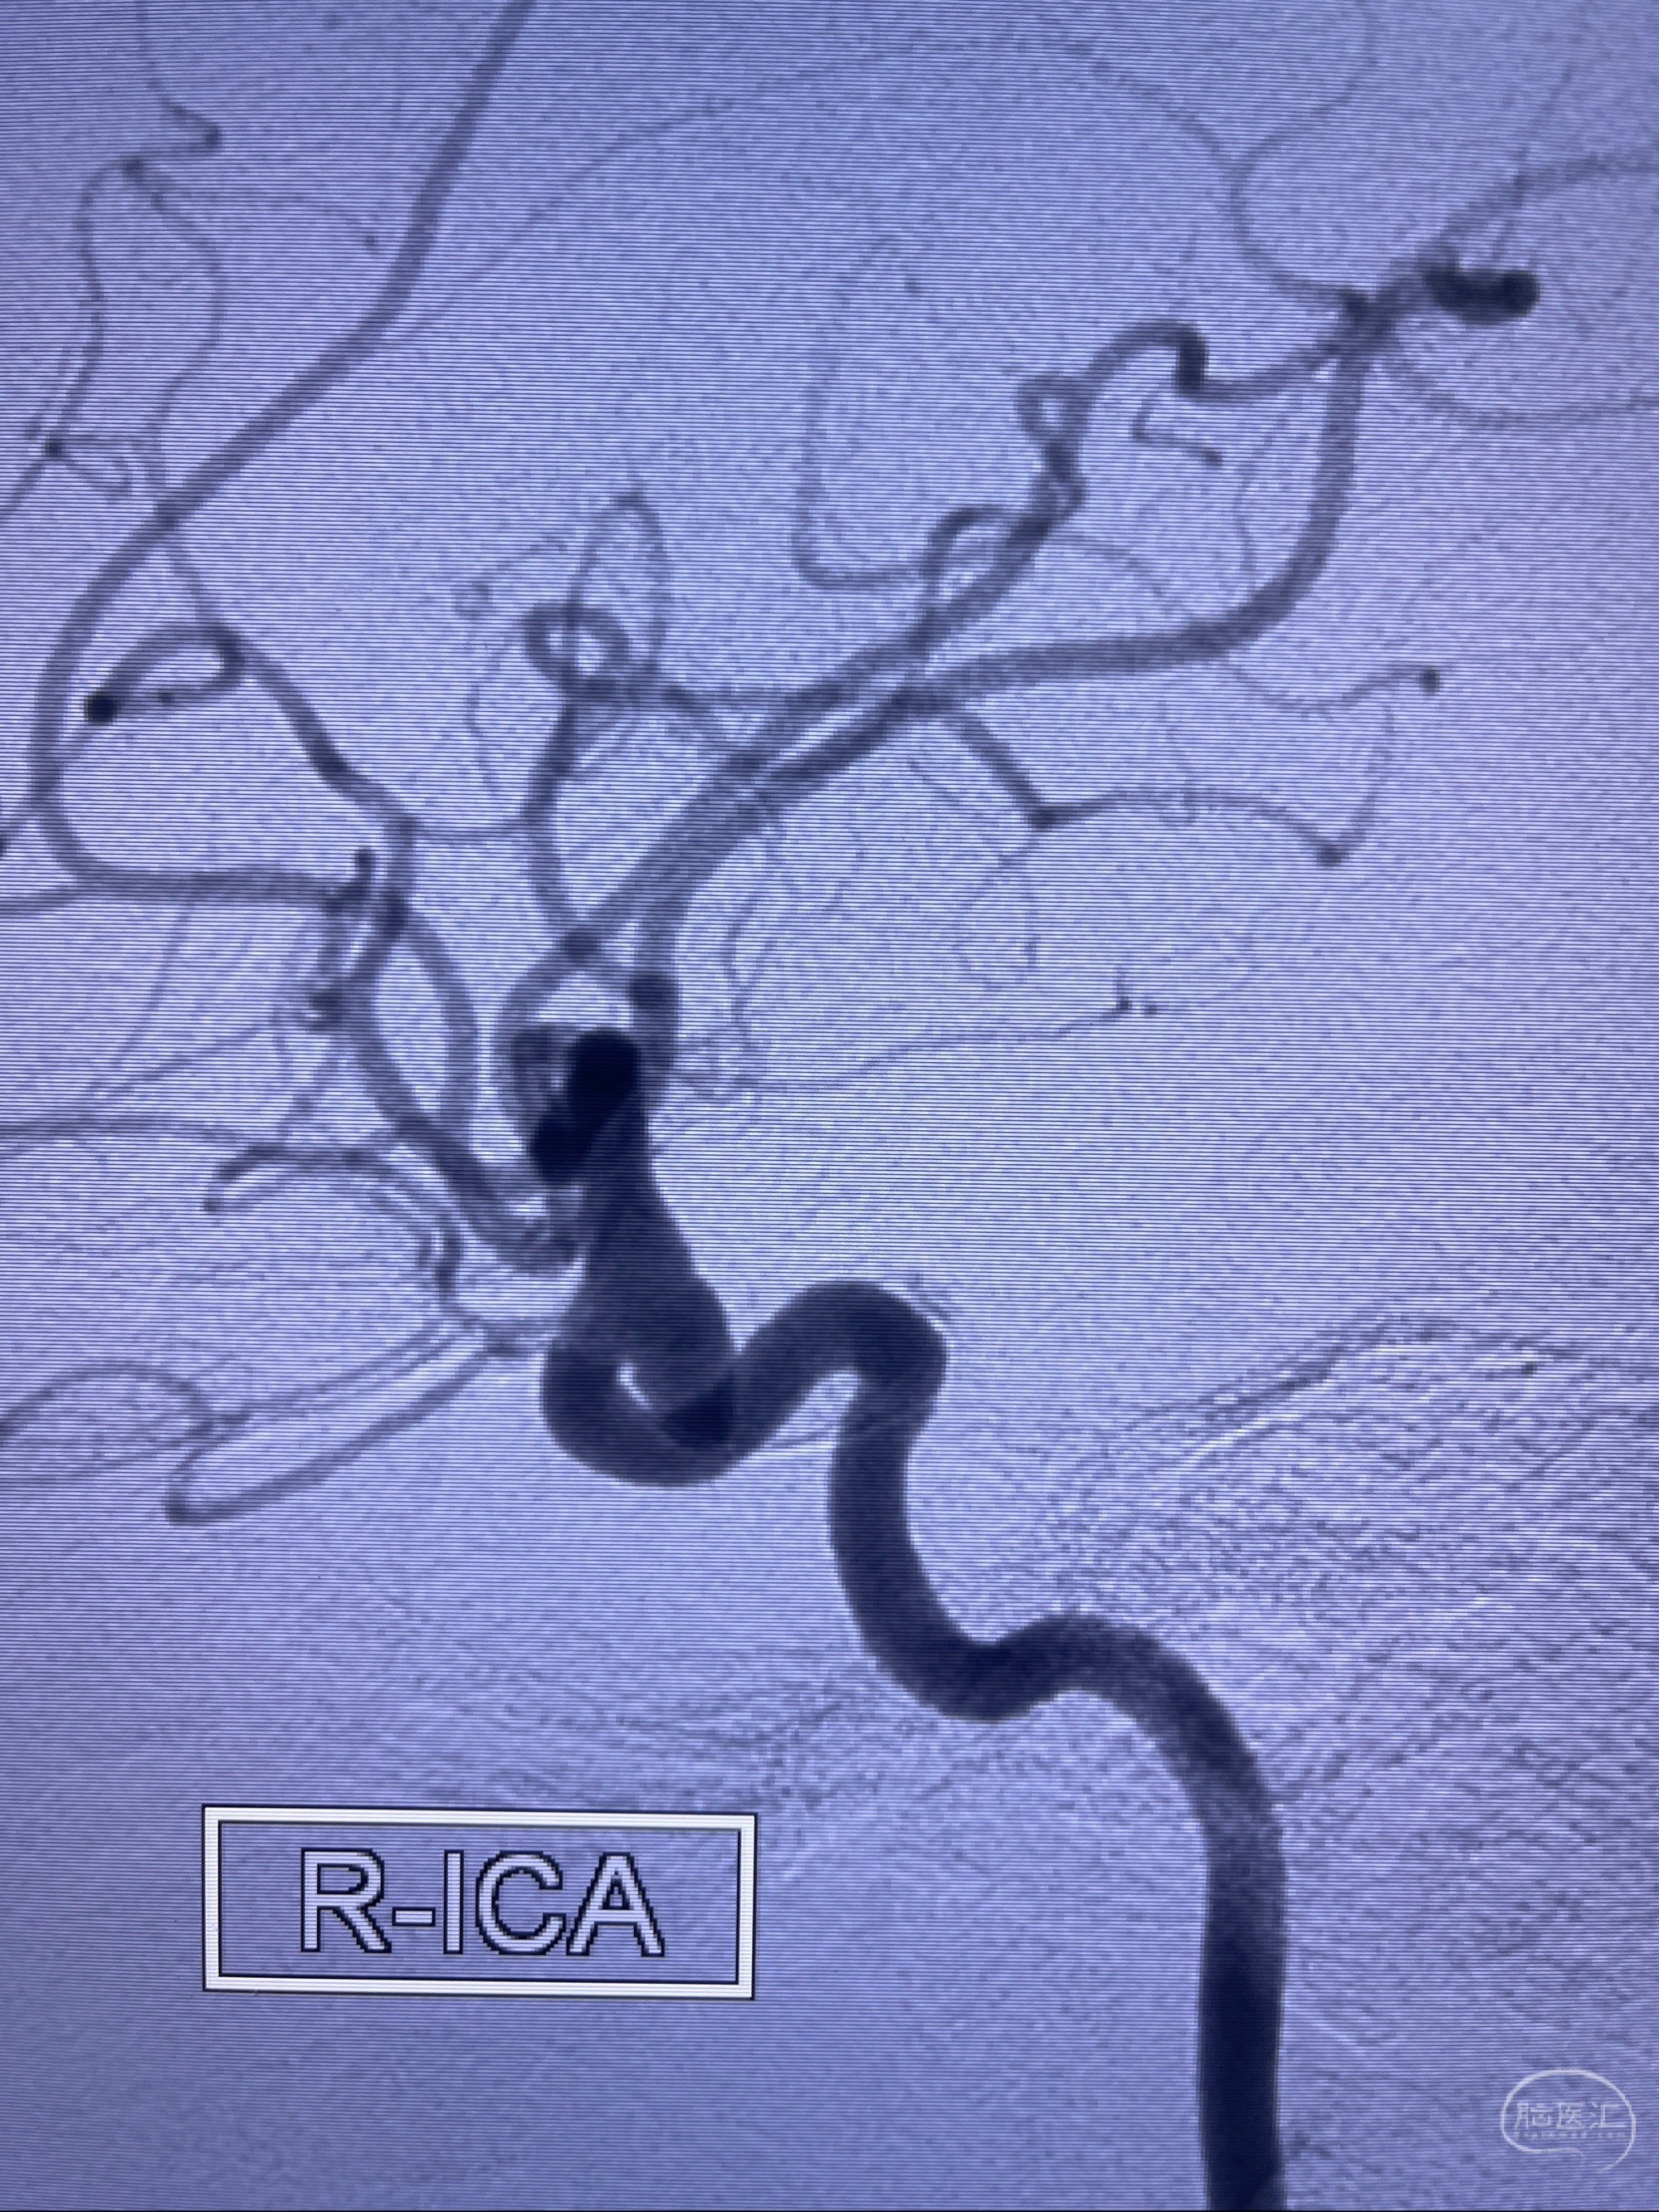

1.右侧颈内动脉眼动脉段动脉瘤

CTA示:右侧颈内动脉C6段见指向下方的突起,余左侧颈内动脉、双侧椎动脉、大脑前动脉、大脑中动脉、大脑后动脉及基底动脉走形正常,未见明显扩张及狭窄,局部未见明显瘤样扩张。

2023-07-27全脑血管造影:双侧颈内动脉眼动脉段动脉瘤,右侧较大

2023-08-01全麻下行双侧颈眼动脉瘤支架辅助栓塞

- pipeling4.5-20mm

- pipeline 4.0-20mm